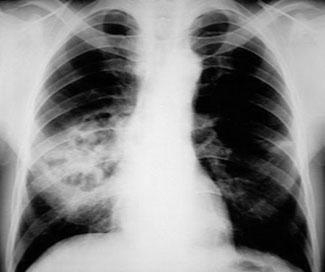

胸部X线检查可诊断和区分肺炎,肺脓肿和脓胸。肺脓肿和肺炎需要药物治疗,而脓胸经常需手术治疗。胸部X线片如下所示。

图4 肺炎球菌性肺炎并发坏死和脓肿

在胸部X线片上,肺脓肿表现为孤立的空洞,具有气液平面。周围斑块状浸润有助于区分肺脓肿与空洞性肺癌。

在胸部X线片,发现脓胸而不是肺脓肿的气液平面向胸壁延伸,气液平面跨过肺裂延伸,并逐渐变细。

胸部X线片上应仔细检查肋膈角,以评估预示积液或脓胸的液体是否出现。

患者直立位胸片,当大约200 mL积液时,肋膈角变钝。